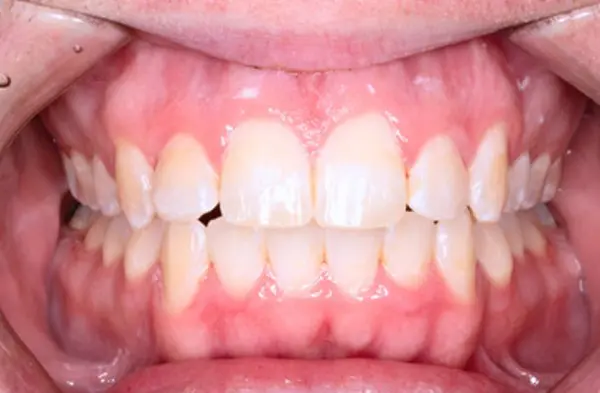

Before

After